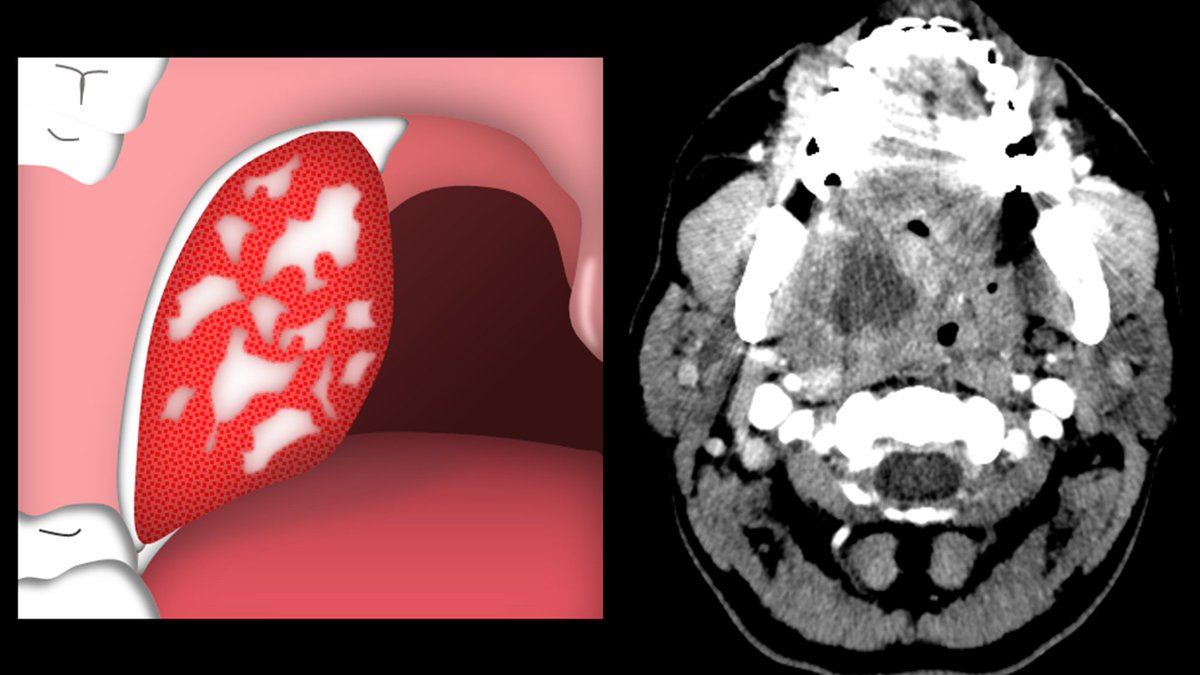

8/On CT, this inflammatory changes causes enlargement of the tonsils and hyperenhancement of the crypts.

This results in the classic "tiger-stripe" appearance of tonsillitis.